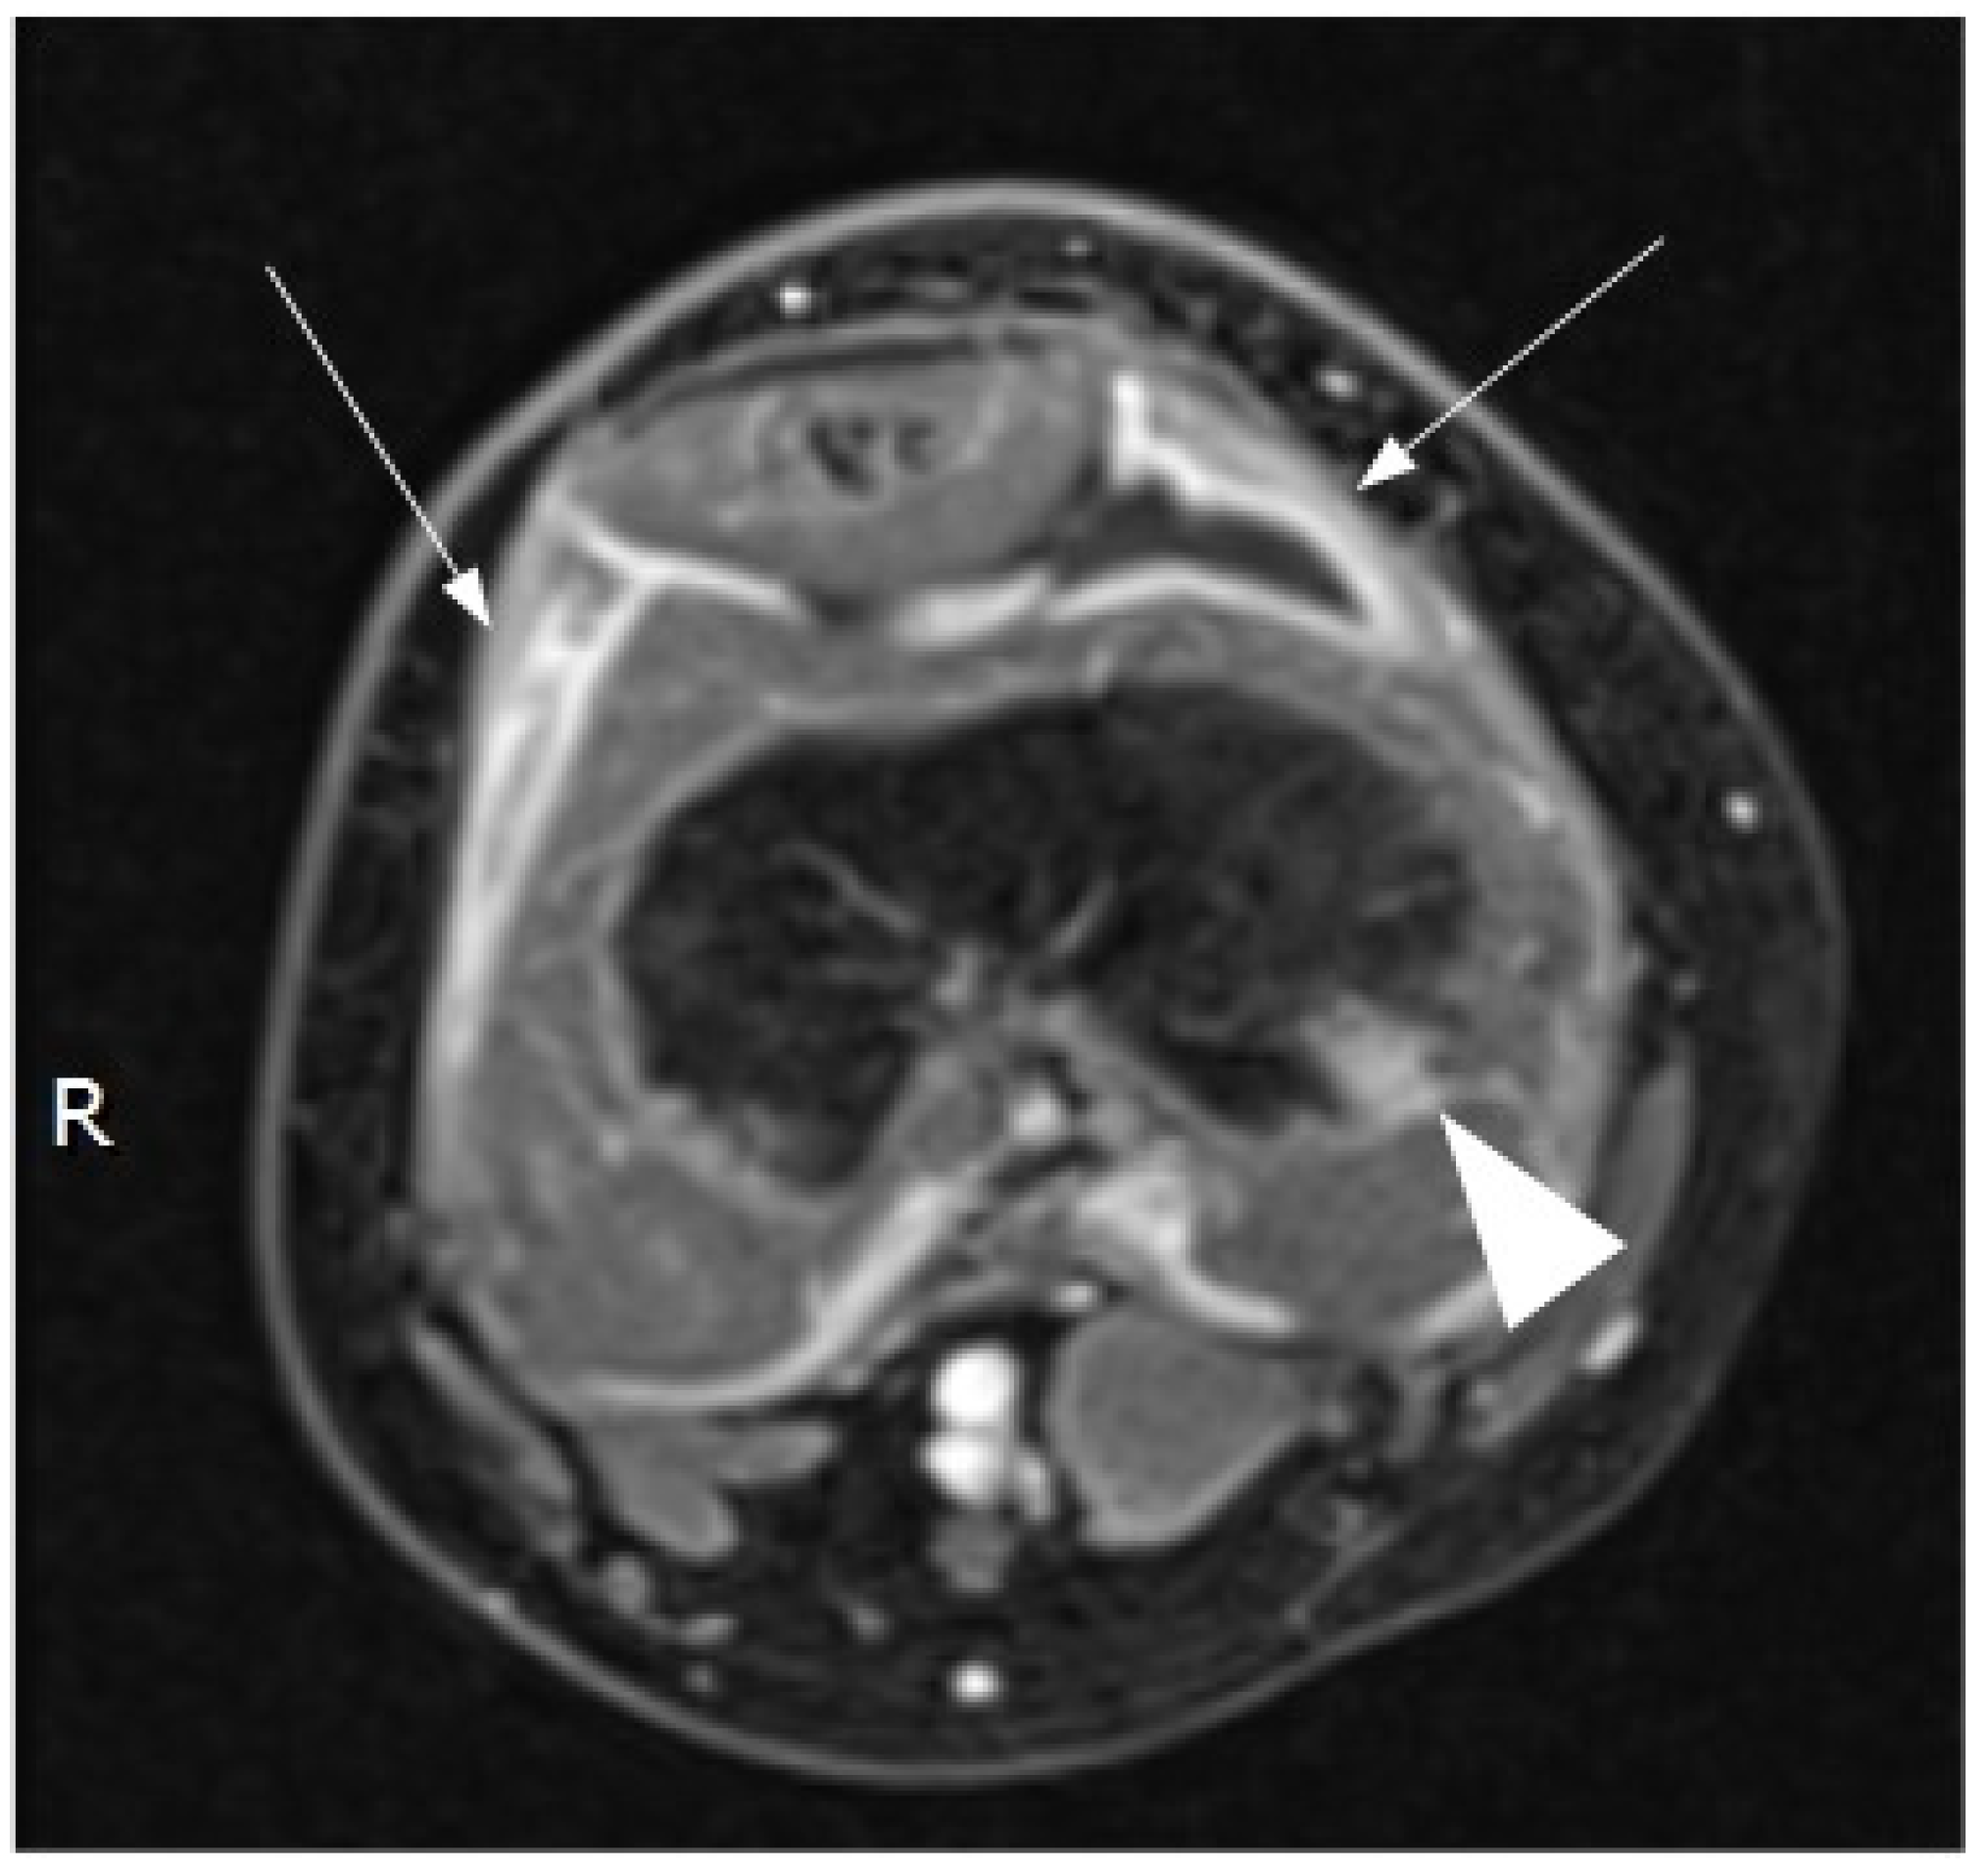

2. Case Report